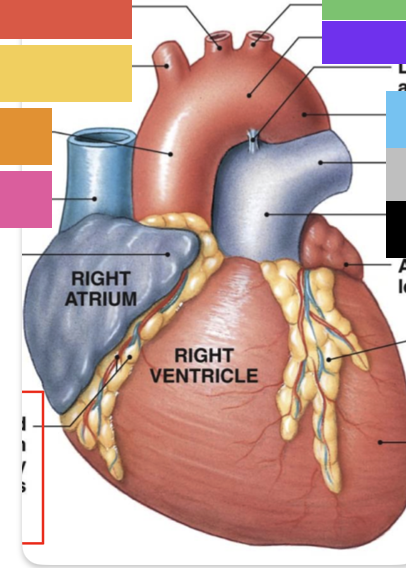

light purple

base

purple

apex

grey

right atrium

pink

right auricle

green

left atrium

green

left auricle

blue

right ventricle

orange

left ventricle

green

coronary (atrioventricular) sulcus

pink

interatrial septum

dark blue

interventricular septum

green

anterior interventricular sulcus

green

posterior interventricular sulcus

orange

aortic valve

yellow

pulmonary valve

red

tricuspid valve (right AV)

purple

bicuspid valve (left AV)

yellow

chordae tendineae

orange

papillary m.

blue

trabeculae carneae - only in ventricles

red

pectinate m. - only in R atrium

pink

fossa ovalis

grey

opening of coronary sinus

green

ligamentum arteriosum

green

fibrous pericardium

blue

parietal pericardium

pink

visceral pericardium (connective tissue) / epicardium (muscle)

purple

myocardium

grey

endocardium

pink

superior vena cava

black arrow

inferior vena cava

black

pulmonary trunk

purple

left pulmonary artery

black

left pulmonary veins

blue

(branches of) right pulmonary artery

yellow

right pulmonary veins

orange

ascending aorta

purple

aortic arch

yellow

brachiocephalic trunk (blue)

pink

right common carotid artery

purple

right subclavian artery

red

left common carotid artery (grey)

green

left subclavian artery (black)

blue

descending aorta

blue

thoracic aorta

yellow

abdominal aorta

red

right coronary artery

yellow

posterior interventricular artery

green

left coronary artery

blue

anterior interventricular artery

pink

circumflex artery

coronary sinus